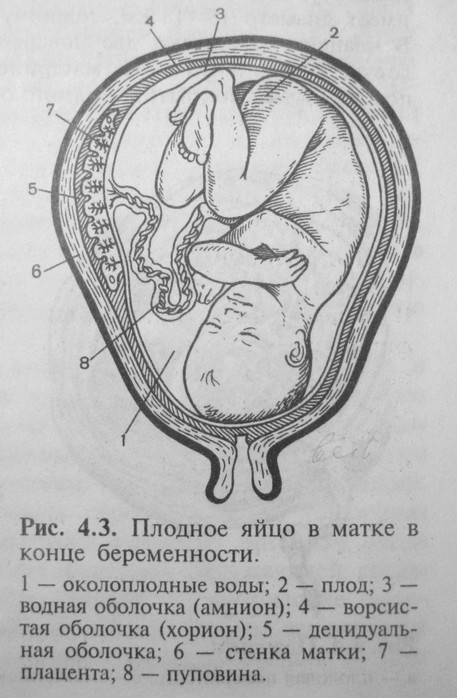

Амнион и Околоплодные Воды: Функции и Роль в Беременности